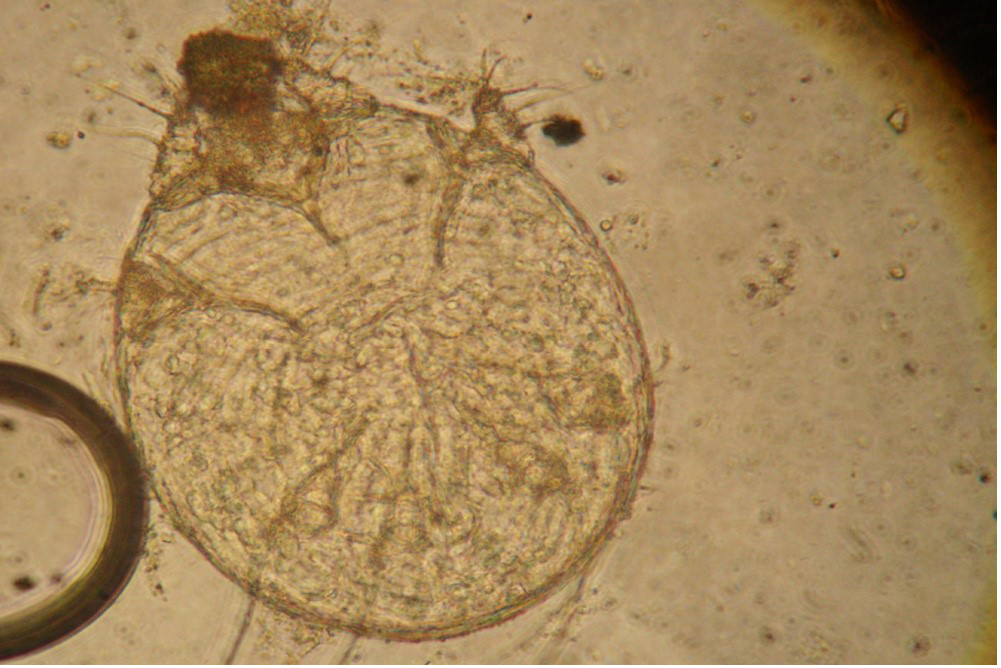

in the red foxSummary There are several different types of mange each caused by a different species of mite but sarcoptic mange most commonly affects foxes Sarcoptic mange is a skin disease caused by the small 2 to 4 mm or less than one quarter of an inch parasitic mite Sarcoptes scabiei several thousand of which may burrow into a single square centimetre of skin Notoedric Mange In Humans britishhamsterassociation uk dermatitis htmDermatitis by Liz Johnson If we suspect dermatitis in a hamster we should first exclude the possibility that what we see is simply a normal scent gland as seen over the best cat art Cat CareCat hair loss is not that uncommon and can be caused by many different ailments and problems Your veterinarian is the best person from whom to obtain advice diagnosis and treatment

catdandruffclinic cat mange feline scabies all you need to Cat Mange is a skin disease caused by various tiny mite species Some of the causative mange mites are normal residents of your cat s skin and hair follicles while others are considered parasites Notoedric Mange In Humans best cat art Cat CareCat hair loss is not that uncommon and can be caused by many different ailments and problems Your veterinarian is the best person from whom to obtain advice diagnosis and treatment vetstreet why does my cat scratch her earsEar scratching is one of the more common reasons cats see veterinarians When the head starts shaking and claws start digging it s a safe bet that a cat has itchy ears But the cause is not always clear

Cat Mange (Feline Scabies): All You Need To Know and More, image source: www.nexusacademicpublishers.com

Notoedres Cati Eggs Related Keywords - Notoedres Cati Eggs ..., image source: classconnection.s3.amazonaws.com

Notoedres Cati Eggs Related Keywords - Notoedres Cati Eggs ..., image source: www.carefordogs.org